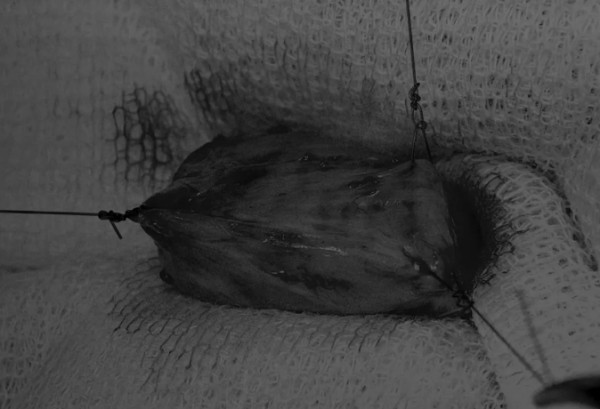

在中线开腹手术后,确定膀胱,将其取出并隔离(图1)。为了使膀胱持续暴露,可在膀胱中线两侧各放置一根固定缝线(图2)。

图2 在手术过程中,还需要另外两根固定缝线来保持膀胱切开术的膀胱边缘处于暴露状态